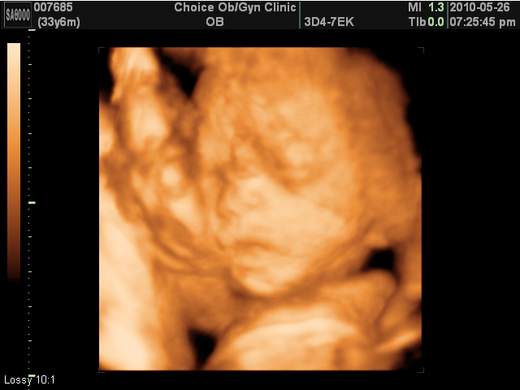

明就是貝貝預產期了

但是到現,只有宮縮哩